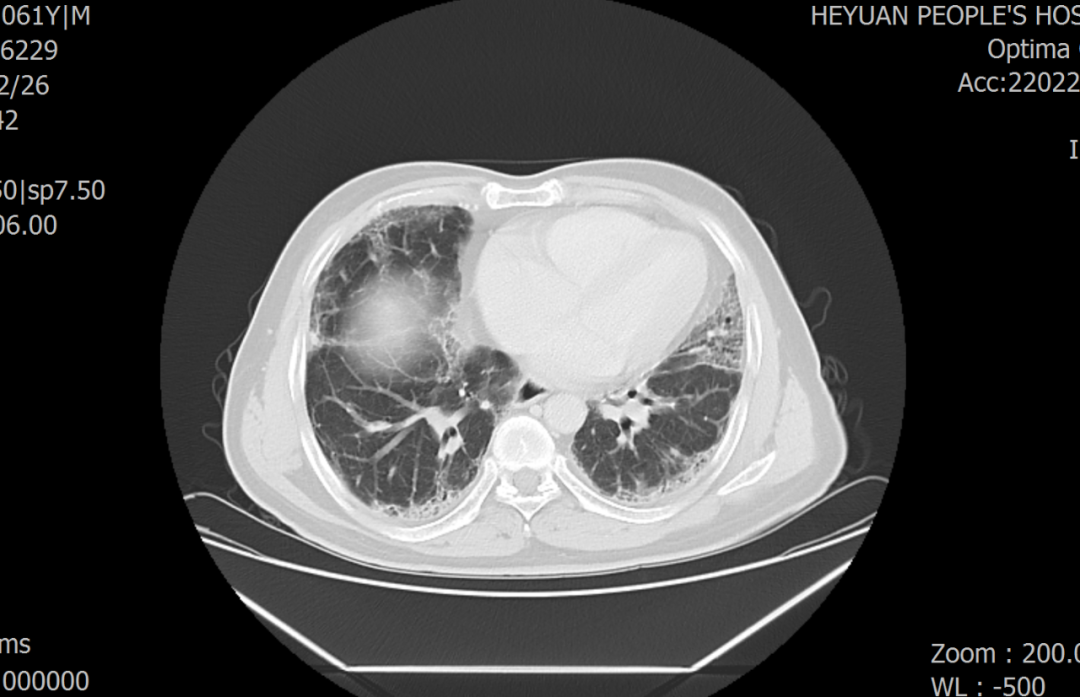

患者蓝某,男,61岁,因“咳嗽、呼吸困难2年余”入院。患者曾多次到广州等地大医院就诊,行胸部HRCT考虑间质性肺炎,但治疗效果不佳。患者呼吸困难症状渐进加重,近几个月来,平地缓慢行走数十米即有明显呼吸困难,严重影响生活质量,遂前来我院求治。罗少华主任查看患者后指出:患者为中年男性,慢性病程,主要症状为咳嗽、呼吸困难,来院时指脉氧饱和度90%(吸入空气状态下),查体提示存在杵状指、双下肺闻及Velcro啰音,胸部CT提示双侧间质性肺炎;但间质性肺炎是一大类疾病的总称,该患者当前影像学及实验室检验无法判断是属于哪一类型间质性肺炎,CT上看蜂窝不显著,有多发磨玻璃影,不符合典型特发性肺纤维化改变,故建议患者行经支气管冷冻肺活检术,了解其病理类型。

患者胸部CT(肺窗)